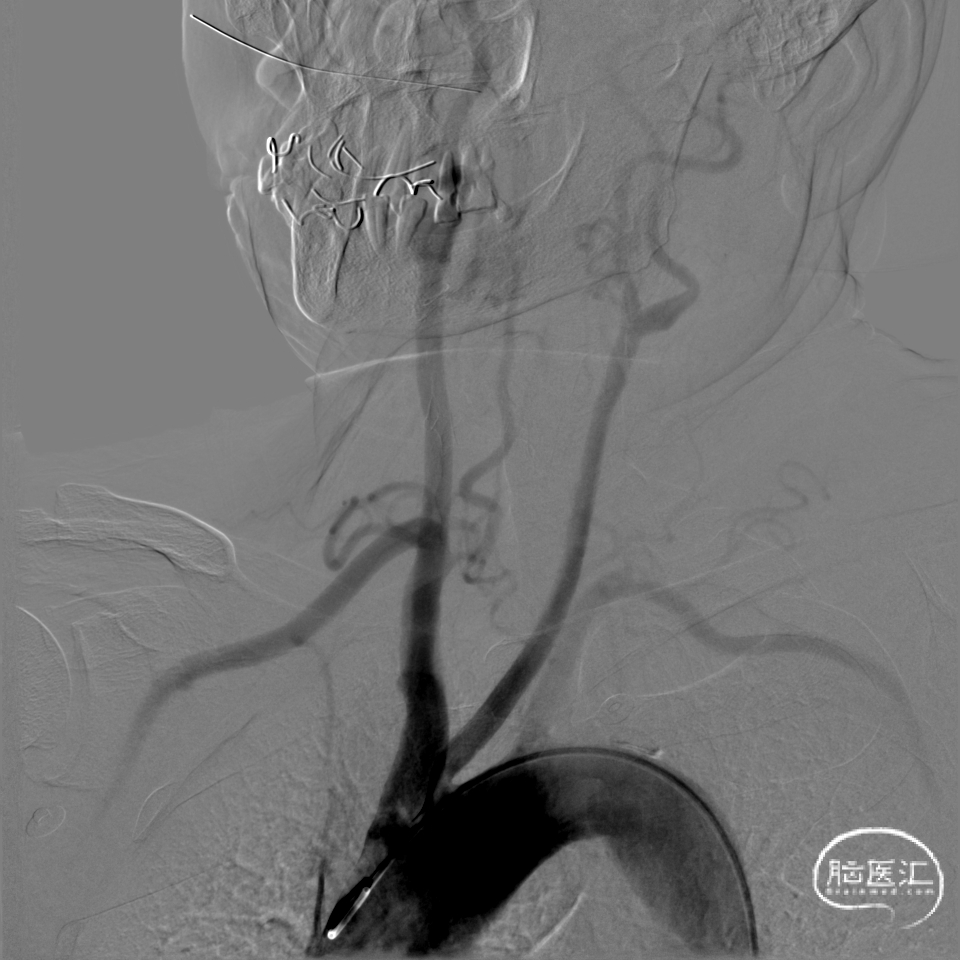

术前DSA影像:

右侧桡动脉穿刺置动脉鞘,泥鳅导丝配合6F 115cm Valent®颅内支撑导管内嵌行至右侧锁骨下动脉近右侧椎动脉起始段处,将导丝配合中间导管上行至椎动脉V3段,撤出泥鳅导丝,手推造影,显示:基底动脉中段可见重度狭窄,狭窄率约80%。

将微导丝头端置右侧大脑后动脉,沿微导丝引入2.0*10mm球囊,小心扩张狭窄段,撤出球囊后造影,原有狭窄较前稍好转,沿微导丝引入支架用微导管置于基底动脉,撤出微导丝,保留微导管,沿微导管引入3.5*15mm Neuroform EZ支架,缓慢释放,复查造影,狭窄较前明显好转,支架贴壁良好。

复查Dyna CT,颅内未见出血及造影剂外渗。